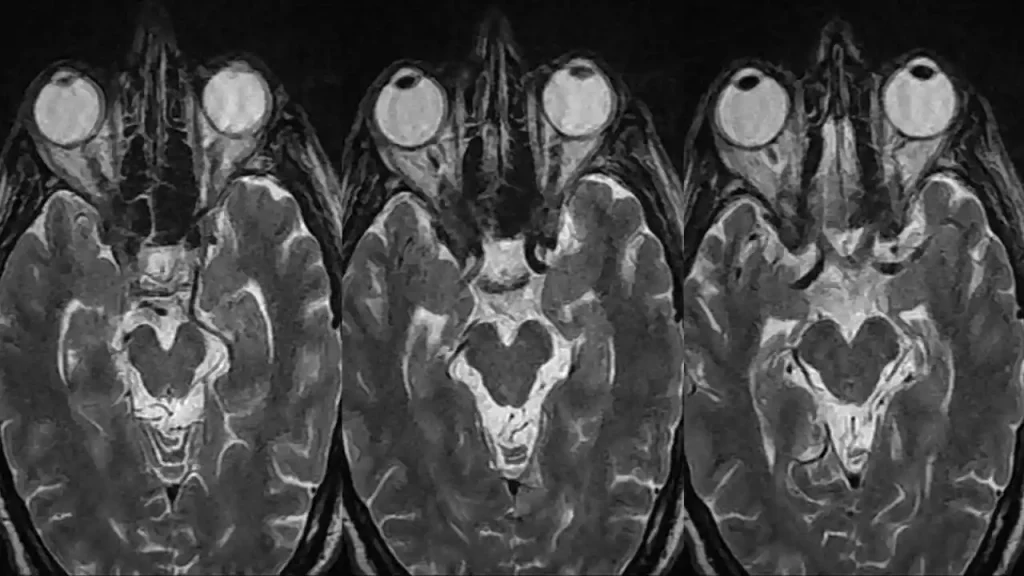

سودو اسکن یک روش پیشرفته و غیرتهاجمی برای ارزیابی فعالیتهای مغزی است که با استفاده از امواج رادیویی، تصاویر دقیقی از عملکرد مغز ارائه میدهد. این روش به ویژه در تشخیص اختلالات عصبی و روانی مانند افسردگی، اضطراب، ADHD و صرع کاربرد دارد.

در مقایسه با روشهای سنتی مانند ام آر آی و CT اسکن که عمدتاً ساختار آناتومیک مغز را بررسی میکنند، سودو اسکن به تحلیل عملکردی مغز میپردازد. به عبارت دیگر، در حالی که MRI و CT اسکن ( بهترین مراکز سی تی اسکن در تهران) تصاویر ساختاری از مغز ارائه میدهند، سودو اسکن فعالیتهای الکتریکی و شیمیایی مغز را مورد بررسی قرار میدهد.